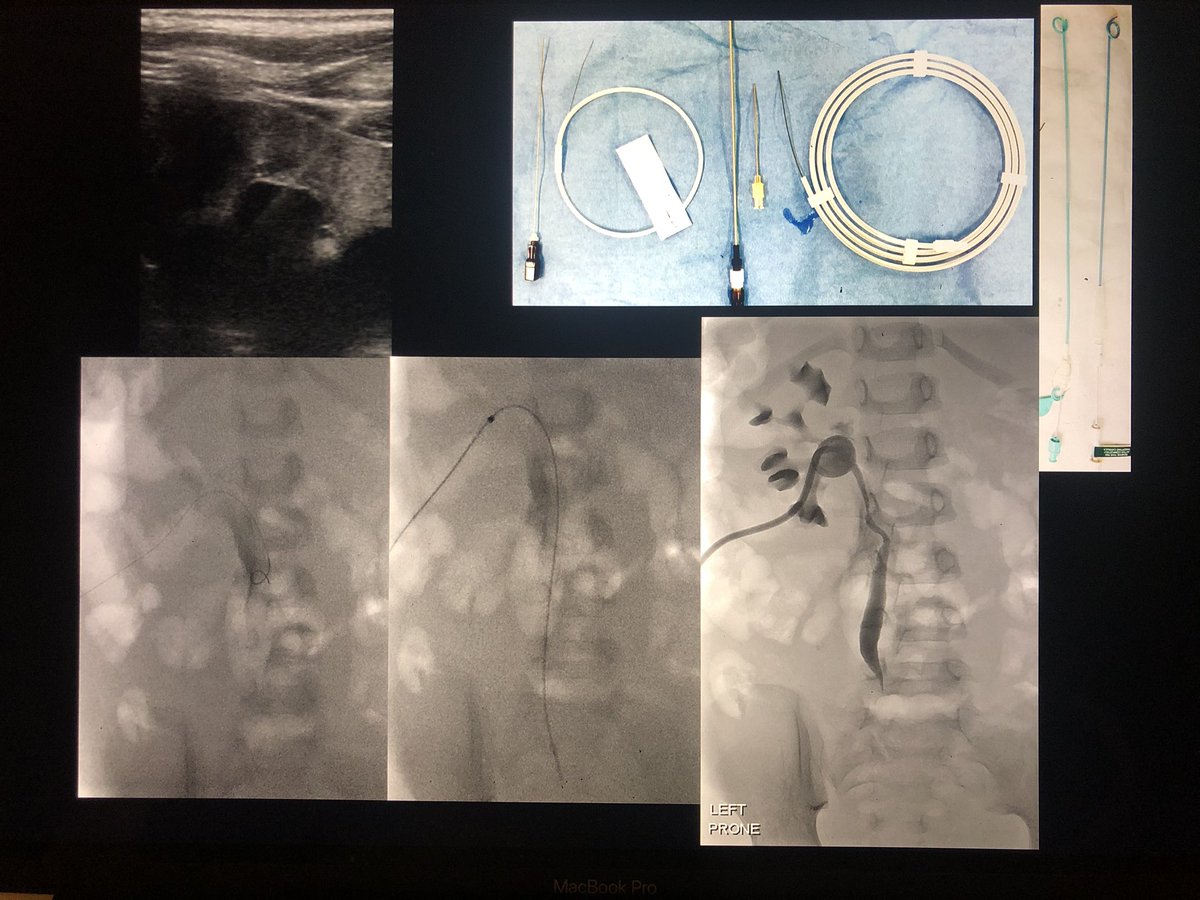

Paediatric nephrostomy

(a short tweetorial)

Technique

•GA

•US guidance for access to PCS

• I I for drain catheter placement

•Seldinger technique with Micropuncture access

–Modified or single exchange

•Trocar (‘single-stick’) technique

2/4